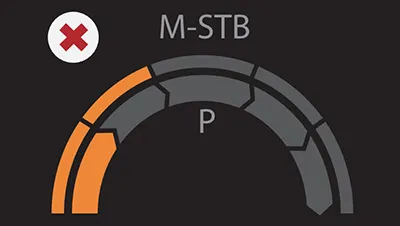

Надежный показатель контроля качества

- Индекс давления (P): качественный контроль давления зонда

- Индекс стабильности движения (m-STB): обеспечивает стабильность дыхания

- Четкая индикация с другим цветом для улучшения контроля качества во время обследования

Нарушение дыхательных движений; слишком низкое давление Prboe

Нарушение дыхательных движений; слишком низкое давление Prboe Состояние дыхания стабильное; Давление зонда слишком высокое

Состояние дыхания стабильное; Давление зонда слишком высокое Дыхательная система стабильна; Давление зонда соответствующее

Дыхательная система стабильна; Давление зонда соответствующееРазличные ультразвуковые решения